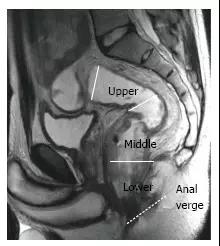

图 2. 根据距肛门边缘的距离,可将直肠分成三段。T2 加权矢状图显示,直肠上段(> 10 厘米),中段(5~10 厘米),和下段(<5 厘米)。